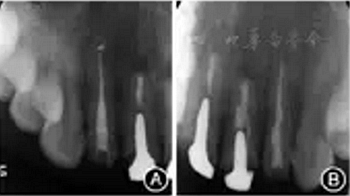

圖7 患者再治療完成后即刻根尖X線片 A:糊劑少量超填,根尖3 mm倒充填致密;B:恰填,根尖3 mm倒充填致密。